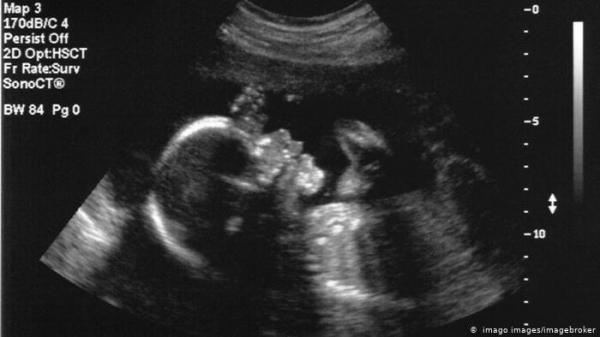

مخاطر التلوث ـ حبيبات البلاستيك تصل للأجنة في رحم الأمهات